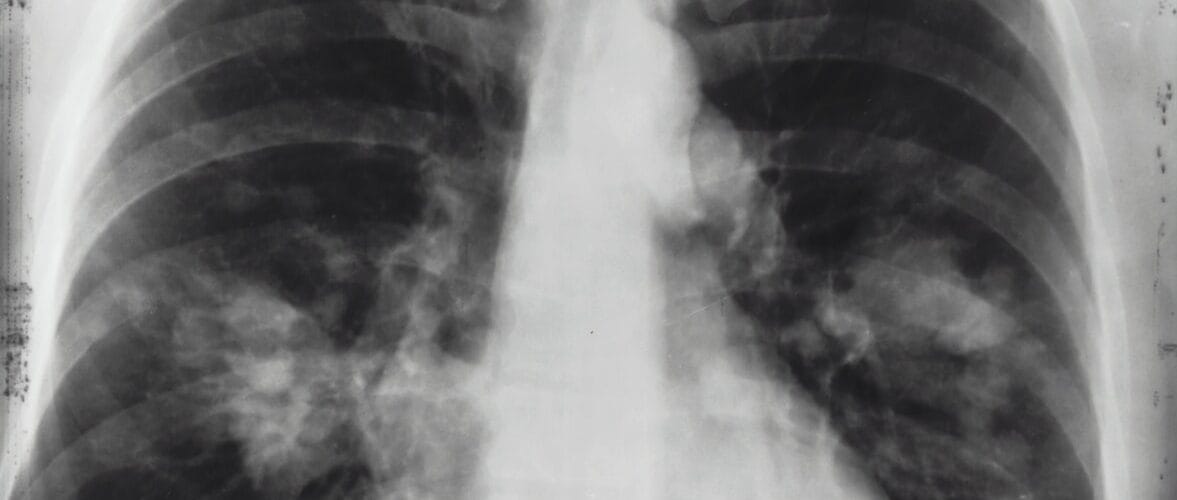

Asthma is an inflammatory disease that affects the airways and lungs. The most common symptoms of asthma are wheezing, coughing, and shortness of breath. People with asthma have sensitive airways that go into spasm when they are exposed to substances such as pollen, dust mites, pet dander or other substances. Approximately 1 in 10 people have some degree of asthma, and over 20 million Americans suffer from the disease.

Asthma is a respiratory condition that causes inflammation of the airways, narrowing them and limiting airflow. It can affect your day-to-day life and range in severity from mild to life-threatening. Here are some alternative techniques you can do at home to relieve asthma symptoms.

Asthma affects more than 300 million people worldwide. It is a chronic inflammatory disorder of the lungs, with symptoms that include wheezing and breathlessness. The causes of asthma are uncertain, but it is thought to be associated with family history, allergies and air pollution.